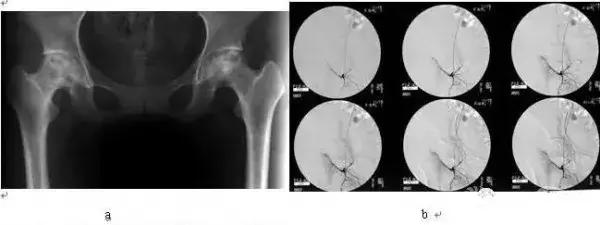

对Ⅱ、Ⅲ期股骨头坏死的血管造影显示,坏死区完全不显影,提示此区域内无血循环(图1)。因此,介入方法注入各种经国家食品药品委员会(CFDA)批准的所有溶栓药物均不能进入无血管的坏死区,将早已机化的血栓溶开达到治疗作用无疑是缺乏科学依据的,除非别有所图的人宣称采用所谓偏方、验方、祖传秘方去欺骗患者。

图1:(a)正常股骨头血管灌注(b)Ⅲ骨坏死标本血管灌注